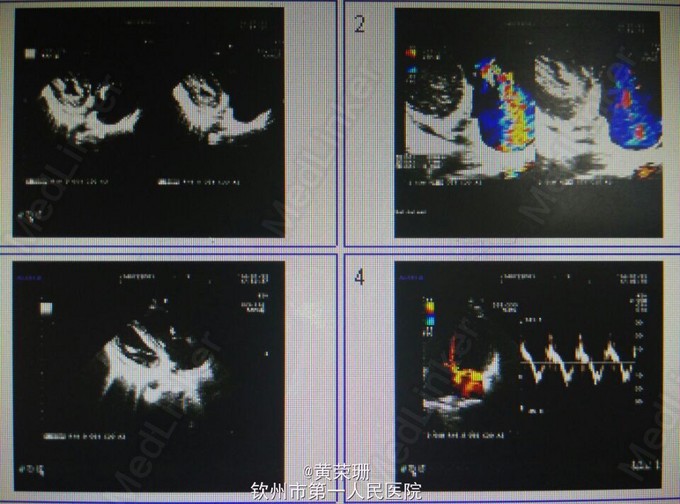

21岁青年男性患者, 急性起病,既往有静脉注射毒品史1月余。因“反复畏寒、发热20余天”入院。自诉20余天前以白开水化“毒品”静脉注射后出现畏寒、发热,体温最高达39.5℃,伴头部胀痛,浑身乏力,伴气促,活动后明显,伴咳嗽、咳痰,间中伴暗红色血丝痰,伴呕吐,为胃内容物,无明显腹痛、腹胀等。于当地门诊予“退热针”治疗后可退热,但易反复,15天出现双下肢几颜面部浮肿,于当地医院住院治疗,检查提示:WBC 25.4*10^9/L,Hb 58.2g/L,痰培养提示:金黄色葡萄球菌,伴少量白色念珠菌伴随生长。心脏B超:三尖瓣脱垂并关闭不全,治疗上余抗感染、输血、利尿等对症处理,但仍间中发热,遂至我院。 入院查体:心率112次/分,贫血貌,两肺呼吸音粗,双肺可闻及湿啰音,心界不大,心率112次/分,率齐,心音有力,三尖瓣听诊区可闻及3/6级收缩期吹风样杂音。 辅助检查:心脏B超:1.三尖瓣前叶赘生物(感染性心内膜炎),伴瓣口反流(重度)及前瓣穿孔,右房增大;2.左心室收缩功能测量值正常范围(图1)。胸部CT:1.考虑两肺感染(真菌感染?细菌感染?),2.两侧胸膜轻度增厚(图2-4)。入院后反复血培养、痰培养均未见培养出细菌几真菌。 主要诊断:1.感染性心内膜炎 三尖瓣赘生物并穿孔 三尖瓣重度关闭不全 2.肺部感染 患者入院后“哌拉西林他唑巴坦+阿米卡星”抗感染、强心、利尿、营养心肌等处理病情平稳后行三尖瓣置换术。术后病理:(三尖瓣)镜下见纤维性瓣膜局部增厚伴大量急慢性炎性细胞浸润,可见小脓肿形成,切表面有红染纤维素样炎性渗出物附着,结合临床符合感染性心内膜炎改变(图5)。